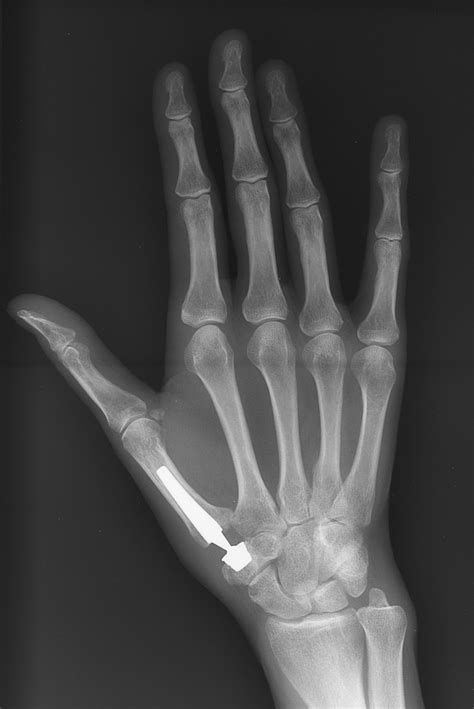

• X-rays: Standard imaging to look for joint space narrowing, bone spurs (osteophytes), and subluxation.

If conservative treatments fail, surgical options for the first carpometacarpal joint are generally highly successful. The most common procedure is a trapeziectomy, where the trapezium bone is removed, and the remaining space is often filled with a tendon graft to provide stability. While recovery requires patience and rehabilitation, most patients experience significant pain relief and improved thumb function following the procedure.